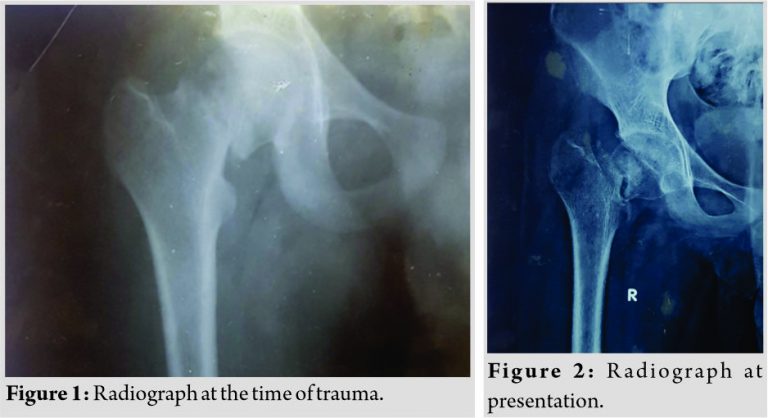

A 16-year-old student presented with complaints of pain over the right hip and inability to walk for 3 months, following a history of fall from a height of around 6 ft. Following the trauma, he was initially taken to a nearby clinic where a radiographic evaluation showed right hip neck of femur fracture (Fig. 1) and he was advised to undergo surgical fixation for the same at a higher center. However, he was not willing and underwent native splinting from an indigenous native bone setter. Following multiple splinting, for a period of 3 months, the splint was removed, but the symptoms did not subside. There was persistence of pain and the patient was unable to weight bear, do his activities of daily living on his own. Following this, he was brought for further management.

On radiographic evaluation of pelvis with both hips, the patient was diagnosed to have right hip displaced neglected neck of femur fracture nonunion (Sandhu Stage 2) (Fig. 2). The patient and attenders were explained regarding the treatment protocol and the possibility of implant back out, non-union, AVN, early arthritis, shortening, and limp.